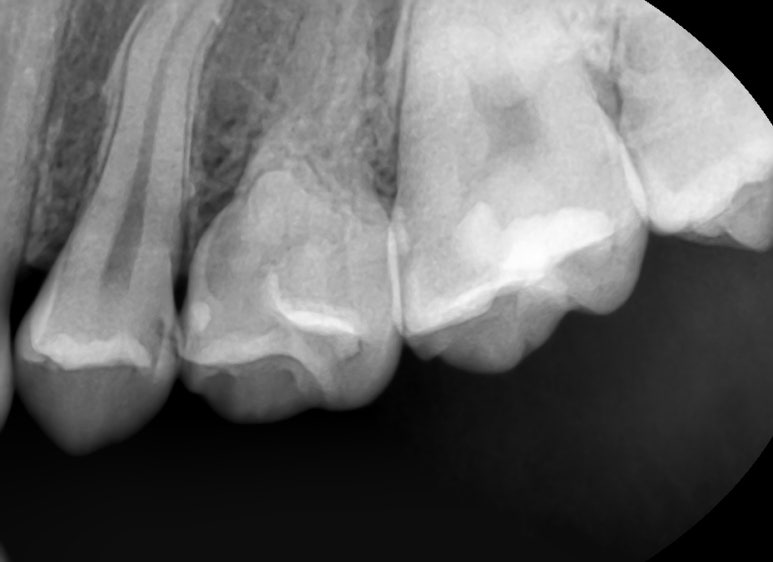

눈으로 봤을때보다는 엑스레이에서 봤을 때 진단되는 경우가 많으며

눈으로 봤을 때는 비쳐보일수있기는 하나 치아사이나 속 충치 등 겉면이 아니라 속에서 썩은 경우에는 엑스레이가 더 확실합니다.

위의 왼쪽 사진에 충치가 없는 것 같으신가요? 치아사이 충치가 있고 치과의사의 눈으로 보면 보이긴 하는데 간혹 충치가 아닌경우도 있어서 더 정확한 판단을 위해서는 엑스레이가 필요합니다.

실제로 엑스레이상에서 충치가 있는것이 확인되었고

충치제거 중 찍은 오른쪽 사진을 보면 충치가 확실히 깊은 있는게 보입니다.

▲이런식으로 오히려 겉에서 보이는 충치보다 사이 충치는 겉에서 까맣게 보이지 않지만 파면 더 깊은 위치에 있습니다.

왼쪽: 겉에서는 보이지 않는 치아사이충치/ 오른쪽: 실제로 치아를 파보면 충치가 깊게 위치하고 있음